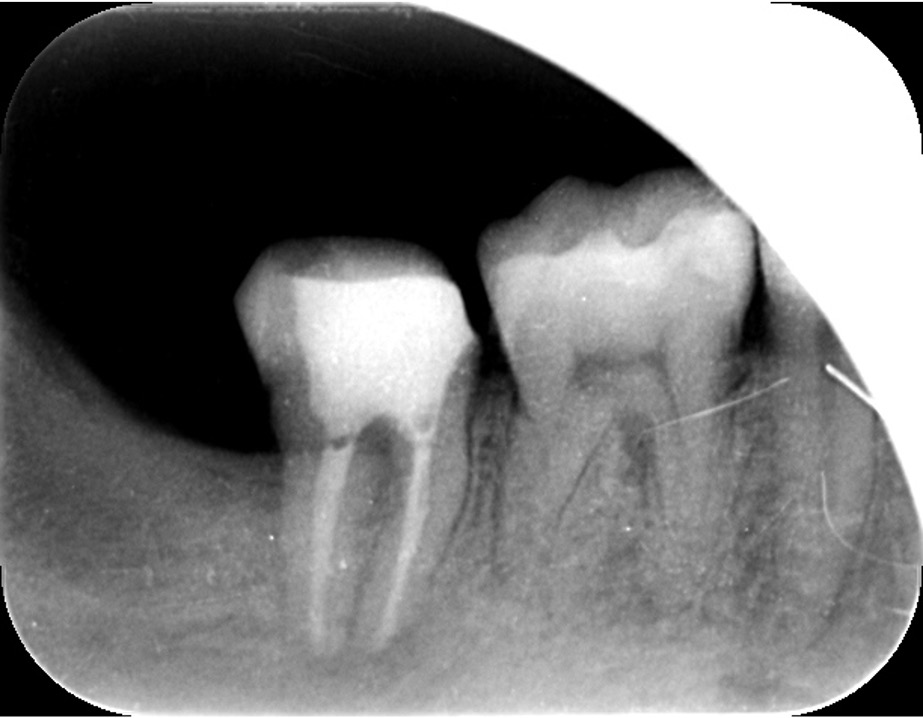

こちらは虫歯で神経を取らないといけなくなりましたが、何度治療しても痛みが消えないと言うことで当院にいらっしゃいました。度重なる治療で歯の神経のあった場所がかなりひろげられており、また根の先端も破壊されている状態でした。ですので、痛みが消えないのです。

肉眼では根の先端は見ることができませんがマイクロスコープでは見ることができます。根の先端をこれ以上破壊しないように清掃して歯の神経があった場所にお薬を詰めることができました。根の治療後、かぶせ物までして半年たっても痛みがありません。

レントゲンを見ていただいて、歯の先までしっかり白いお薬が入っているのがわかります。